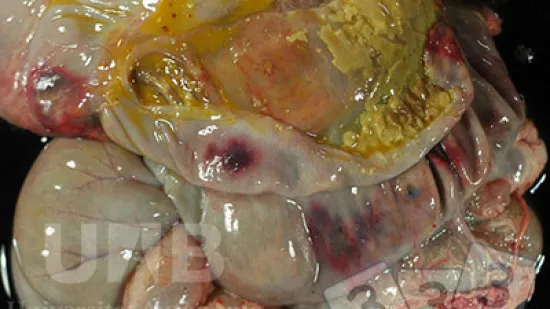

Semaine du 10-Jan-2022

Cette colite fibrineuse et ulcérative n'est PAS associée à....